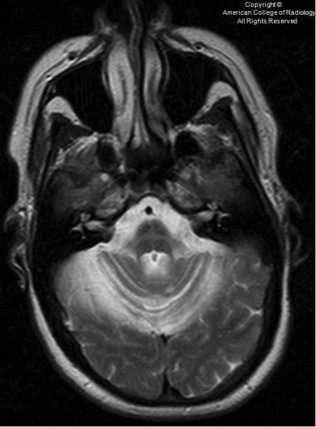

18、脑桥中央髓鞘溶解症(CPM)、渗透性髓鞘溶解症(OM):渗透性髓鞘溶解症为脱髓鞘障碍,见于长期饮酒、营养不良及电解质异常患者(包括儿童)。此类疾病的发生常与快速纠正低血钠相关。许多患者可无症状,一些表现为四肢麻痹、假性球麻痹、急性精神状态改变。典型的脑桥病变位于中央区。T2WI上可见脑桥基底部高信号灶,治疗可好转。中枢髓鞘溶解症是一种发生在中枢的不同脱髓鞘病。根据发生部位的不同,分为脑桥中央髓鞘溶解症(central pontine myelinolysis,CPM)和脑桥外髓鞘溶解症(extrapontine myelinolysis,EPM)。当CPM与EPM同时存在时,被称为渗透性髓鞘溶解症(OM)。

(横断位T2WI及FLAIR示脑桥区高信号灶,DWI示明显弥散受限)